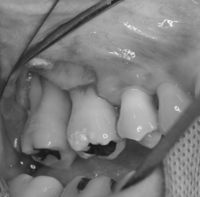

今回行った歯周外科処置は、麻酔下で歯肉を剥離して、根面に付着したプラークや歯石を除去し、歯槽骨(歯を支えている骨)の吸収が著しい部分に自家骨移植を行い、歯肉を復位縫合するといった術式です。

写真で、一番奥の歯の周囲の骨が著しく吸収してしまっているのが確認できます。